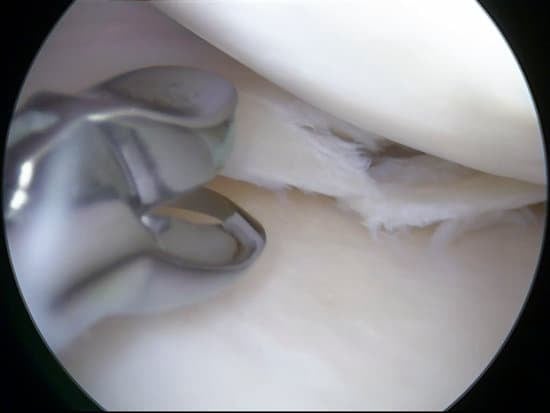

연골 이식술은 연골 손상이나 퇴행을 치료하기 위해 사용되는 수술적 방법입니다.

자가 연골 이식술(OATS, Osteochondral Autograft Transplantation Surgery)은 손상된 관절 연골을 치료하는 수술적 방법 중 하나입니다.

이 방법은 환자 자신의 건강한 연골 조직을 비중량 부하 부위에서 채취하여 손상된 연골 부위에 이식하는 것을 포함합니다.

OATS는 특히 소규모에서 중간 규모의 연골 손상을 치료하는 데 유용하며, 특히 무릎 관절에서 자주 사용됩니다.